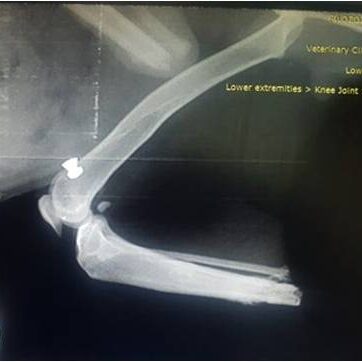

Η διαδικασία ξεκινά με μία αξονική τομογραφία στο Ιατρικό μας κέντρο στην Λευκάδα ή σε κάποιο συνεργαζόμενο με τον κτηνίατρο σας ιατρικό κέντρο. Μέσω αυτής λαμβάνουμε τα απαραίτητα CΤ-images όπου γίνεται ανάλυση  ψηφιακών δεδομένων με χρήση εξειδικευμένου ιατρικού λογισμικού Osirix-FDA.

Το επόμενο στάδιο είναι αυτό της προ-εγχειρητικής μελέτης-διάγνωσης, με σύγχρονες μεθόδους και εξοπλισμό όπως:

Με χρήση εξειδικευμένου μηχανολογικού λογισμικού CAD/CAM/CAE αναπτύσσουμε σε 3D ψηφιακή μορφή:

• την ανατομική περιοχή του οστού σε μορφή 3D όπου θα εφαρμοστεί το εμφύτευμα.